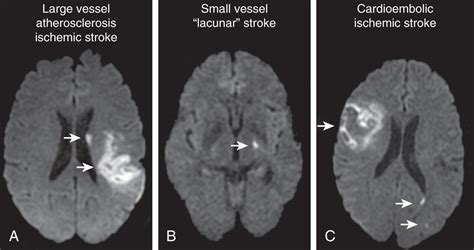

Differentiating Stroke Types

Another critical role of the CT scan is distinguishing between an ischemic stroke and a hemorrhagic stroke . A hemorrhagic stroke will show up as a bright area on the CT scan, indicating bleeding in the brain. For ischemic strokes, the scan will often initially appear normal or show the subtle signs mentioned above. This difference is super important because treatments vary dramatically. If the CT scan shows bleeding, clot-busting drugs are usually not an option. Instead, the focus is on controlling the bleeding and managing the pressure in the brain.

- MRI (Magnetic Resonance Imaging): An MRI can provide even more detailed images of the brain and may be used in cases where the CT scan is unclear or to assess the full extent of the damage. An MRI is better for detecting early changes in the brain tissue.